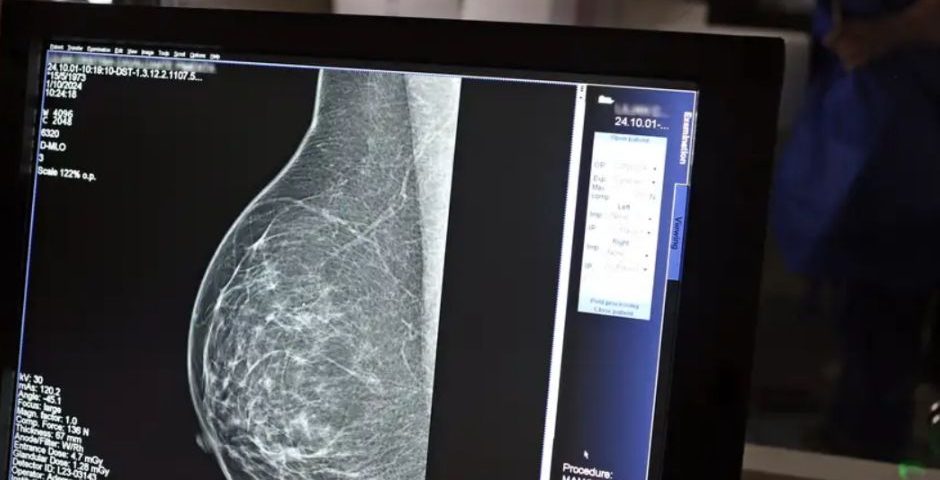

No Outubro Rosa, o Instituto Nacional de Câncer (Inca) estimou 73.610 novos casos este ano no país. É o câncer que mais mata mulheres no Brasil. As mulheres em tratamento pela doença têm o direito de receber o auxílio-doença ou o benefício de prestação continuada.

A vice-presidente da Comissão de Previdência Social Pública da Ordem dos Advogados do Brasil do Rio de Janeiro (OAB-RJ), Danielle Guimarães, destaca que o câncer de mama é uma das doenças que mais afetam mulheres no Brasil, impactando não apenas a saúde física e emocional, mas também a capacidade de trabalho e a segurança financeira das pacientes.